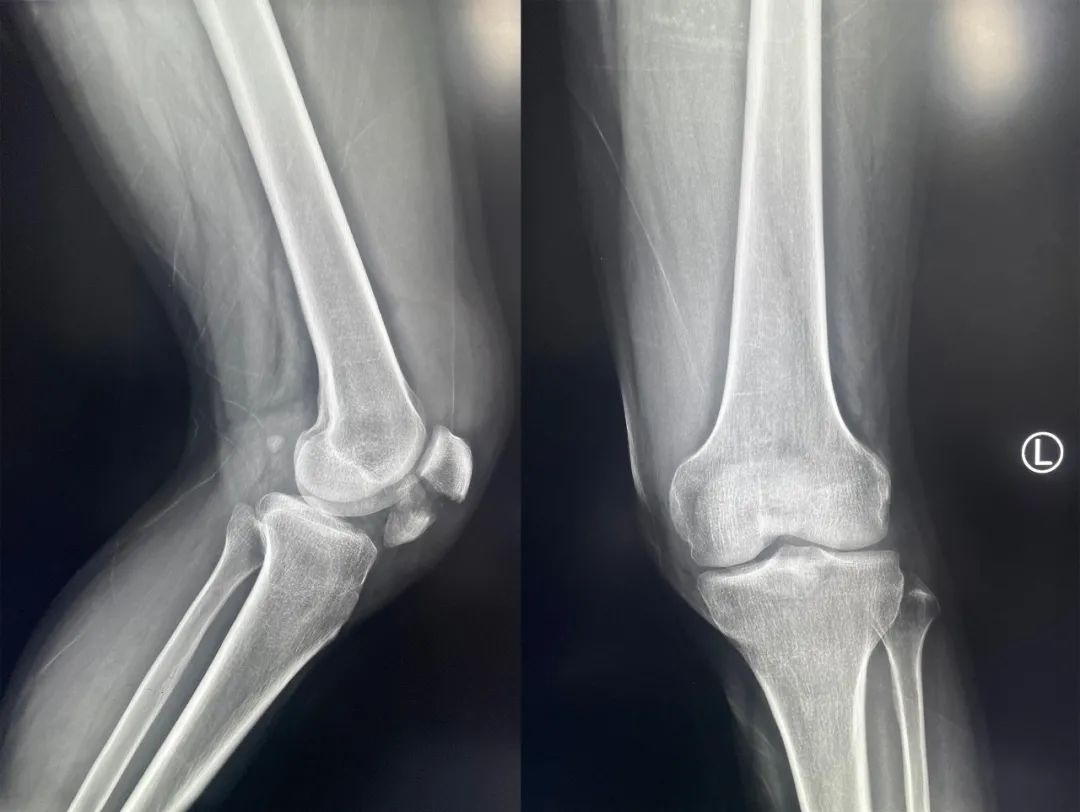

髌骨骨折约占所有骨折的 1%,主要由直接暴力造成,如跌倒时跪地或膝关节屈曲时受到打击。典型的体征包括关节肿胀、压痛、伸膝功能部分或完全丧失。

髌骨骨折正侧位  图源:作者提供

除以主诉和典型体征外,膝关节 X 线片也是必不可少的一项辅助检查,以膝关节正侧位 X 线片最常见,如果怀疑纵向骨折,膝关节屈曲 45° 时髌骨 30° 切位片可以辅助诊断。